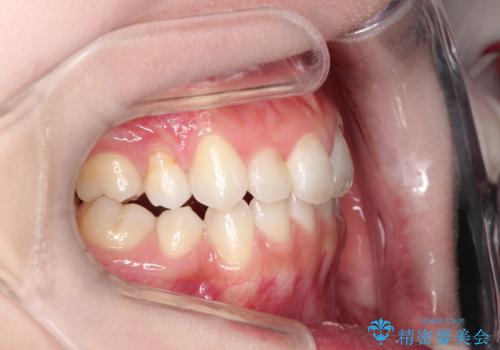

前歯の後戻りを部分矯正で整った歯並びへ

- 矯正治療後の上の前歯の後戻りを気にされて来院されました。

上の前歯のみにブラケットをつけて矯正治療を行いました。

部分矯正は、わずかなガタつき、ずれには有効的です。

ただし、場合によっては部分矯正では対応できないこともあり、その時は全体矯正が必要となります。